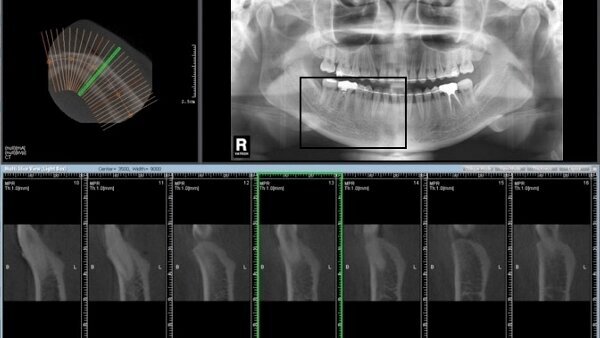

Η δυνατότητα εξέτασης της κρανιοπροσωπικής ανατομίας με τη βοήθεια της τρισδιάστατης απεικόνισης που έχουμε μέσω της CBCT, έχει παρουσιαστεί σαν η νέα "χρυσή" κατάκτηση στη χειρουργική του στόματος. Πρόσφατα μιλήσαμε γι' αυτό το θέμα με τον καθηγητή S. Habfeld στα πλαίσια του ετήσιου Παγκόσμιου Συνεδρίου της FDI στο Χόνγκ Κόνγκ.

ΑΠΑΝΤΗΣΗ: Σήμερα αυτή η τεχνολογία εφαρμόζεται ευρέως σε περίπλοκες επεμβάσεις στοματικής και γναθοπροσωπικής χειρουργικής. Π.χ. εξετάζουμε συνήθως με αυτήν μεγάλες κύστεις και βαθιά έγκλειστους τρίτους γομφίους. Μπορεί επίσης να μας βοηθήσει στη διάγνωση παθήσεων του ιγμορείου καθώς και στην Τραυματιολογία ή στην αποκατάσταση ανωμαλιών και δυσπλασιών των γνάθων.

ΑΠΑΝΤΗΣΗ: Σε αντίθεση με την παραδοσιακή απεικόνιση, η CBCT μας επιτρέπει τη λεπτομερή εξέταση και αξιολόγηση της ανατομίας και των παθολογικών καταστάσεων σε τρισδιάστατη βάση. Αυτό μπορεί να είναι εξαιρετικά χρήσιμο για το προγραμματισμό της θεραπείας και την αξιολόγηση περιοχών και σημείων που ενέχουν χειρουργικό κίνδυνο όπως τα παρακείμενα νεύρα, τα δόντια ή τα αιμοφόρα αγγεία. Σε πολλές περιπτώσεις περιμένουμε μία σημαντική μείωση των εγχειρητικών κινδύνων και μία βελτίωση στον προγραμματισμό της επέμβασης.